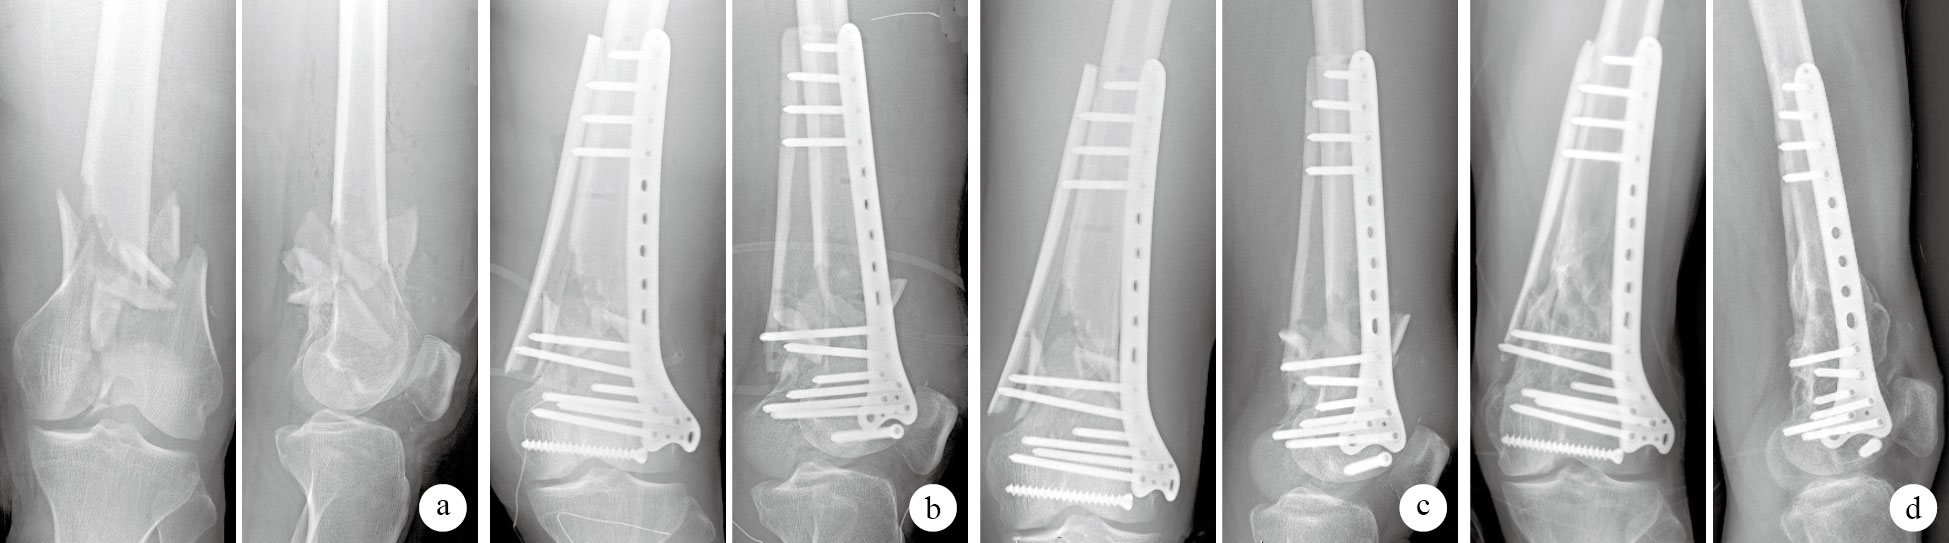

本組手術時間90~125 min,平均110 min;術中出血量280~350 mL,平均328 mL。術后復查X線片示骨折復位及鋼板、骨板在位良好。術后1周1例GustiloⅡ型骨折患者局部皮緣出現淺層壞死,局麻下行郵票植皮后愈合;其余切口均Ⅰ期愈合。18例均獲隨訪,隨訪時間12~36個月,平均23個月。X線片復查示骨折于術后3~12個月愈合,平均5.6個月;無內固定物松動及再骨折發生。末次隨訪時,1例GustiloⅢ型患者因關節面缺損嚴重致膝關節功能恢復差伴輕度外翻畸形,屈膝85°,伸膝35°;1例合并同側脛骨近端骨折者膝關節功能恢復不良,屈膝100°,伸膝30°;余患者屈膝120~140°,伸膝0~15°。均無感染、免疫排斥反應等并發癥發生。末次隨訪時按Merchan等療效評定標準行膝關節功能評定:獲優7例,良9例,可1例,差1例,優良率88.9%。見圖 1。